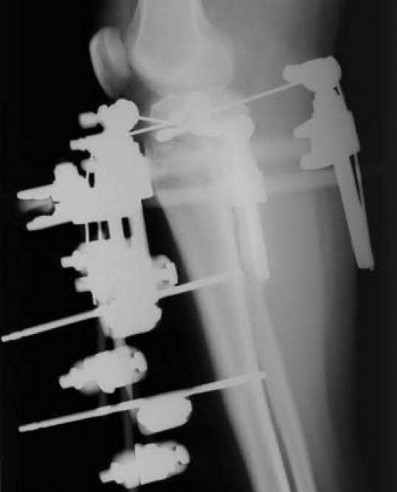

A 28-year-old male sustains a closed comminuted tibial shaft fracture.

Two hours post-injury, he develops severe leg pain unyielding to narcotics. His blood pressure is 120/80 mmHg. Intracompartmental pressure monitoring is performed. Based on current guidelines, which measurement dictates an emergent 4-compartment fasciotomy?

Explanation

Acute compartment syndrome is classically defined by tissue hypoperfusion. The absolute compartment pressure is less reliable than the differential pressure (Delta P). A Delta P (Diastolic Blood Pressure minus Compartment Pressure) of less than 30 mmHg is an absolute indication for emergency fasciotomy, as capillary perfusion gradient is lost when tissue pressure approaches the diastolic pressure.